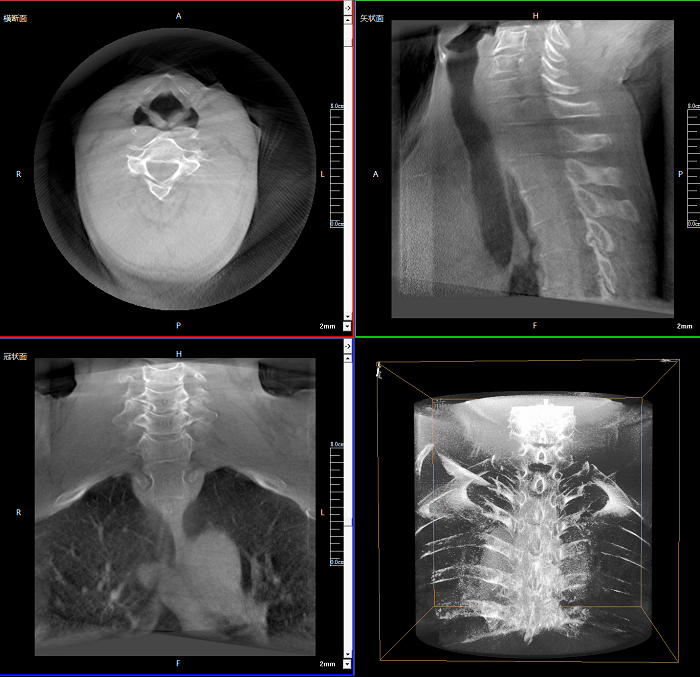

該設備可進行快速的術中三維掃描,生成類CT斷層圖像和立體3D圖像,保障植入物置入效果。廣泛適用于骨科、脊柱外科、矯形外科、創傷骨科等其他領域。

術中實時生成橫斷面、矢狀面、冠狀面及三維影像,可在任意切面、任意角度評估植入物和解剖結構的相對位置。

智能影像后處理算法

工作站系統自行處理采集圖像,智能識別人體組織與金屬植入物信息,清晰呈現手術興趣區圖像。